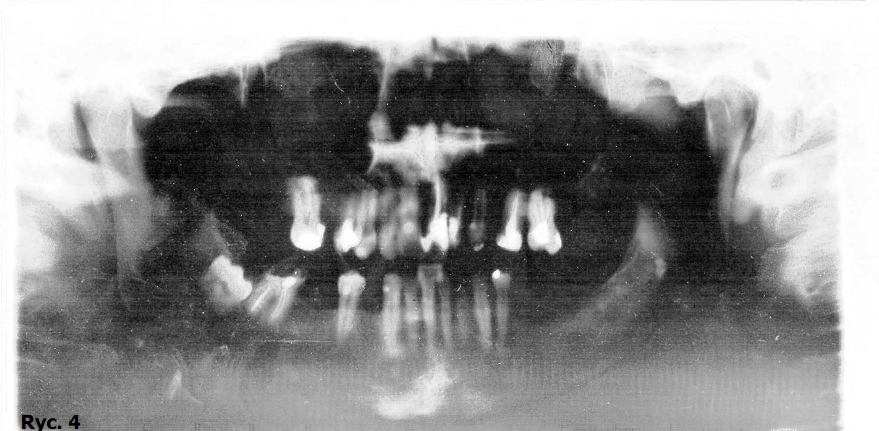

Pacjent B.J., lat 45, zgłosił się do gabinetu w celu poprawy estetyki i uzupełnienia braków zębowych. W badaniu zewnątrzustnym zaobserwowano wysunięcie bródki, wygładzenie bruzdy bródkowo wargowej, pacjent miał charakterystyczne wzmożone napięcie warg i kłopoty z wymową niektórych głosek. W badaniu wewnątrzustnym stwierdzono odwrotne zachodzenie zębów siecznych, zęby ustawione w III klasie Angle’a. Wynik dodatni testu czynnościowego bez poprawy rysów twarzy pozwolił postawić rozpoznanie: przodozgryz całkowity (ryc. 1, 2, 3).